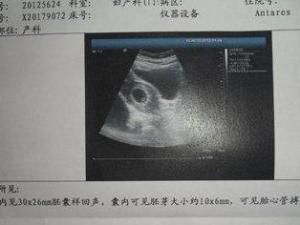

5周:胎兒長到0.4厘米,進入了胚胎期,羊膜腔擴大,原始心血管出現,可有搏動。B超可看見小胎囊,胎囊約占宮腔不到1/4,或可見胎芽。

6周:胎兒長到0.85厘米,胎兒頭部、腦泡、額面器官、呼吸、消化、神經等器官分化,B超胎囊清晰可見,並見胎芽及胎心跳。

7周:胎兒長到1.33厘米,胚胎已具有人雛形,體節已全部分化,四肢分出,各系統進一步發育。B超清楚看到胎芽及胎心跳,胎囊約占宮腔的l/3。